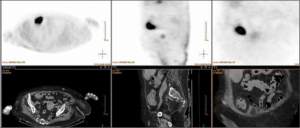

Madame S., hospitalisée pour chutes, syndrome inflammatoire et altération de l’état général

Que déduire de l’image TEP-Scanner ? p. 101

Pr Benoît de Wazières et Dr Fannie Santoni (Nîmes)

Que déduire de l’image TEP-Scanner ? Madame S. est hospitalisée à la suite de chutes à répétition, syndrome inflammatoire biologique et altération de l’état général. D’après l’interrogatoire de la famille,…